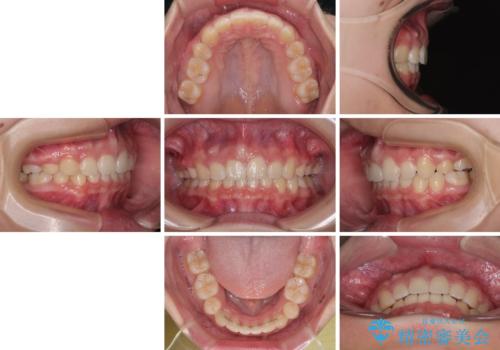

上下正中位置を改善するため、左下はイレギュラーに第二小臼歯を抜歯しました。そのため治療期間の長期化が予想されましたが、2年半ほどで期待通りの歯列に仕上げることができました。

- 2年7ヶ月

- 30回以上